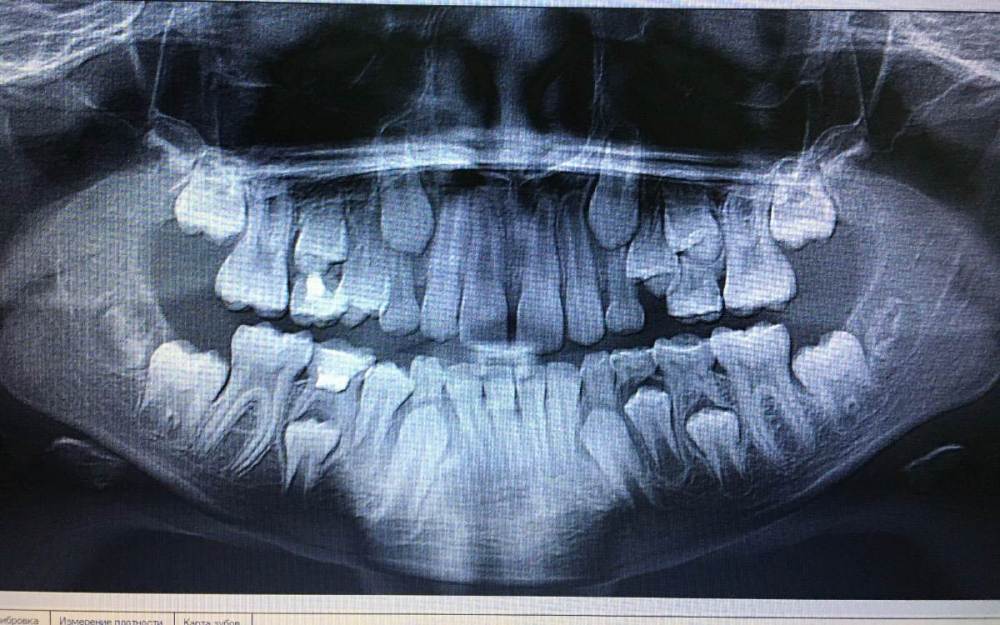

Прошу помочь. Ребёнок 10 лет. Носил несъёмный аппарат, для расширения челюсти. Сейчас левая, верхняя 4ка уперлась в соседний зуб.

1. Платная клиника. Ждём 2 месяца, есть шанс прорежется. Если нет, предлагают частичную брекет систему на 6 зубов.

2. Районная клиника. Ждать смыла нет, может быть хуже. Брекеты нет, поставить съемную пластинку.

И глупый вопрос. А если удалить 5й зуб, корни рассосались, не спасёт ситуацию?